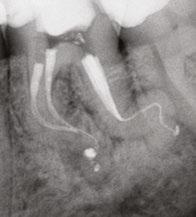

Figure 4 (left): Preoperative image of tooth No. 15. Figure 5 (right): Postoperative image. Rotary negotiation with Roto-reciprocation in all 3 canals with lengths from 25-28 mm and the ProTaper Ultimate Slider advanced to WL within 2 passes

Figure 6 (left): Preoperative image of tooth No. 30. Figure 7 (right): Postoperative image. Rotary negotiation with Roto-reciprocation in all 4 canals and the ProTaper Ultimate Slider advanced to WL within 2 passes without the use of a hand file